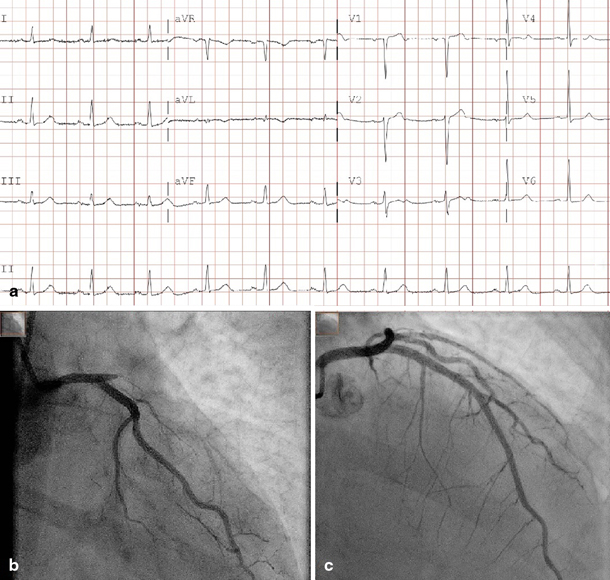

A 70-year-old male was diagnosed with non-ST-elevation myocardial infarction (NSTEMI) without signs of haemodynamic compromise and intermediate GRACE risk scores (Fig. 1a). Initial cardiac biomarkers were elevated with a creatine kinase of 1236 U/l and positive high sensitive troponin of 787 ng/l. He was scheduled for coronary angiography within 24 h. One and a half hours after admission the pain had not resolved despite medical therapy, and it was decided to perform immediate angiography. To our surprise, occlusion of a large left anterior descending artery (LAD) was found with collaterals from the right coronary artery. Subsequent successful percutaneous coronary intervention of the LAD was performed (Fig. 1b and c). The procedure was successful with TIMI-3 flow and myocardial blush grade 3. After the procedure the patient remained free of symptoms and during further observation no complications occurred.

a Electrocardiogram on admission. 25 mm/s, 10 mm/mV. b Left coronary artery in RAO caudal angulation. Before intervention. c Left anterior descending artery in RAO cranial view. After PCI with implantation of a 3.5 mm drug-eluting stent